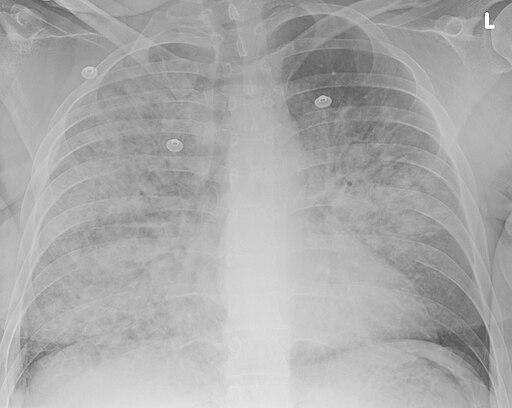

Aspiration pneumonia

© Doc James, CC BY-SA 4.0, via Wikimedia Commons

A chest X-ray.